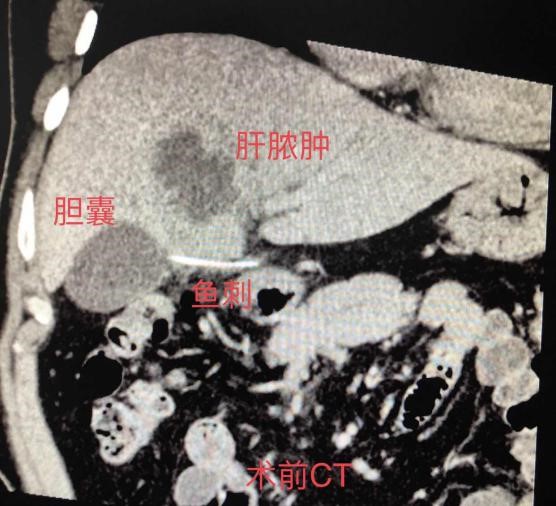

入院后行腹部强化CT显示肝左叶脓肿,胆囊与胃窦部间隙内异物(长约4cm),异物形状像极“鱼刺”。通过仔细询问得知患者2周前曾误吞鱼刺,因无明显不适感,未在意。结合病史考虑鱼刺穿过胃窦,移位至胃窦至胆囊之间,扎进肝脏导致肝脓肿。

患者主要症状为肝脓肿导致的感染发热,先行超声引导下肝脓肿穿刺置管引流。引流后患者体温恢复正常,复查CT显示脓肿体积缩小。“鱼刺”位置未发生变化,决定行腹腔镜下探查取出“鱼刺”。术中经仔细分离后,将鱼刺完整取出。术后测量鱼刺长约4cm,与术前CT检查显示一致。